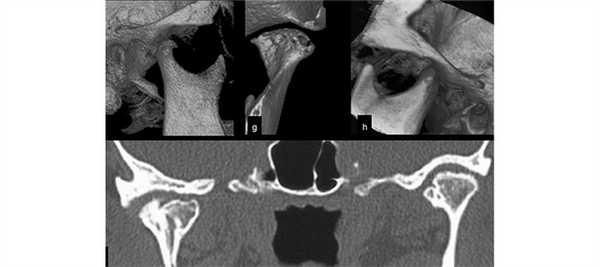

При проведении КТ, предполагаемая патология или дефект становятся хорошо видны на мониторе компьютера. Изображение может быть получено в нескольких проекциях - аксиальной, фронтальной или сагиттальной.

Полученный снимок может определить следующие виды отклонений:

- Изменение размеров суставной щели.

- Отклонения суставного диска.

- Изменение костных структур.

- Наличие новообразований.

- Смещение головок сустава.

КТ ВНЧС может проводиться с закрытым и открытым ртом, в зависимости от конкретного клинического случая. Во время проведения процедуры могут использоваться различные варианты этого обследования:

- Траснаксиальная методика. Это стандартная процедура (через ось тела). В ходе ее проведения получается порядка 25 снимков, идущих параллельно глазной ямке. Можно визуализировать отдельно левый и правый сустав.

- Саггитальное сканирование. Оно проводится строго параллельно ушной раковине. Ведется оценка состояния ВНЧС в трех фазах, т.е. пациента просят закрыть рот, приоткрыть его наполовину и полностью.

- Объемный 3D-режим. Получается пространственное изображение правого и левого сустава.